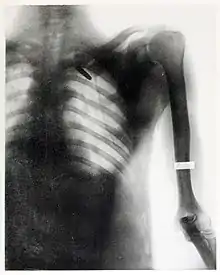

In December 1898, she began to provide services as a radiographer to the United States Army, who had been sending wounded soldiers from the Spanish-American War's Pacific theater back to the United States through San Francisco.[14]

On August 20, 1899, she took one of her most famous radiographs, an image showing a Mauser 7 mm bullet lodged in the brain of John Gretzer Jr., in the region of the left occipital lobe.[12][15] Private Gretzer, of the 1st Nebraska Volunteers, wounded at Mariboa, Philippines on 27 March 1899 during the Spanish–American War. The private later returned to duty as a mail clerk.[16] Accounts of the case were reported in the 1902 edition of The International Text-Book of Surgery and in newspapers.[17] Another case of a bullet lodged in a soldier's skull, X-rayed by Fleischman was also reported in newspapers in 1899.[18]

She received praise for her work during the Spanish-American War from the Surgeon General of the Army George Miller Sternberg.[19] Several of her radiographs were also used by William C. Borden to illustrate his book on the medical use of X-rays in the Spanish-American War.[15]